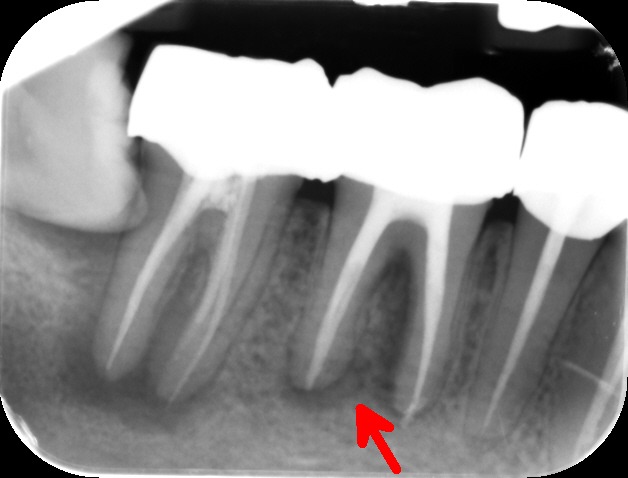

During the consultation, the dentist will first listen to your concerns and carry out appropriate tests to identify the right tooth that is causing pain. As a part of the diagnosis, your dentist will carry out various clinical tests to identify the right tooth and will take some radiographs which can aid in the diagnosis.

An access cavity is placed on the surface where the patient bites, to reach the root canals of the tooth. Once all the canals are identified, small files are used to remove the infected pulp.

Files of different sizes are used to eliminate bacteria and infection and to shape the canals. The canals are disinfected thoroughly with irrigants and later the canals will be sealed in 3 dimensions with a special medicament called gutta-percha to prevent reinfection of the tooth and the access cavity will be sealed with a temporary filling.